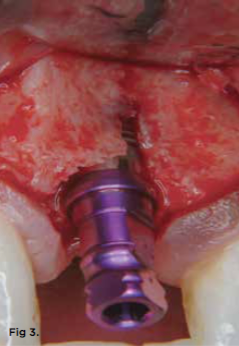

Typically, bone is cut prior to implant placement with the use of standard drill burs. While drill bits rotate, the cutting resistance vector has been described as "constantly changing," and this can cause the drill bit to shave along the bone surface away from the initial osteotomy site, inducing less-than-optimal site preparations (Figure 2 through Figure 4).37 Since fresh, hydrated trabecular bone is a ductile material, it has a good capacity for plastic deformation. Osseodensification is essentially a burnishing process that redistributes bone material on the bony surface through plastic deformation.37 The counterclockwise rotation of osseodensification burs causes the lands of the bur to slide across the surface of the bone by means of low plastic deformation that is purposefully designed to have a compressive force less than the ultimate strength of the bone.

Fig 4. Implant placement using standard burs may potentially lead to off-axis drilling, which at times may compromise implant outcomes or long-term esthetic results. These three photographs show examples of cases in which multiple implant threads were left exposed due to thin buccal bone relative to the implant placement (clinical photographs courtesy of Salah Huwais, DDS).

Figure 4